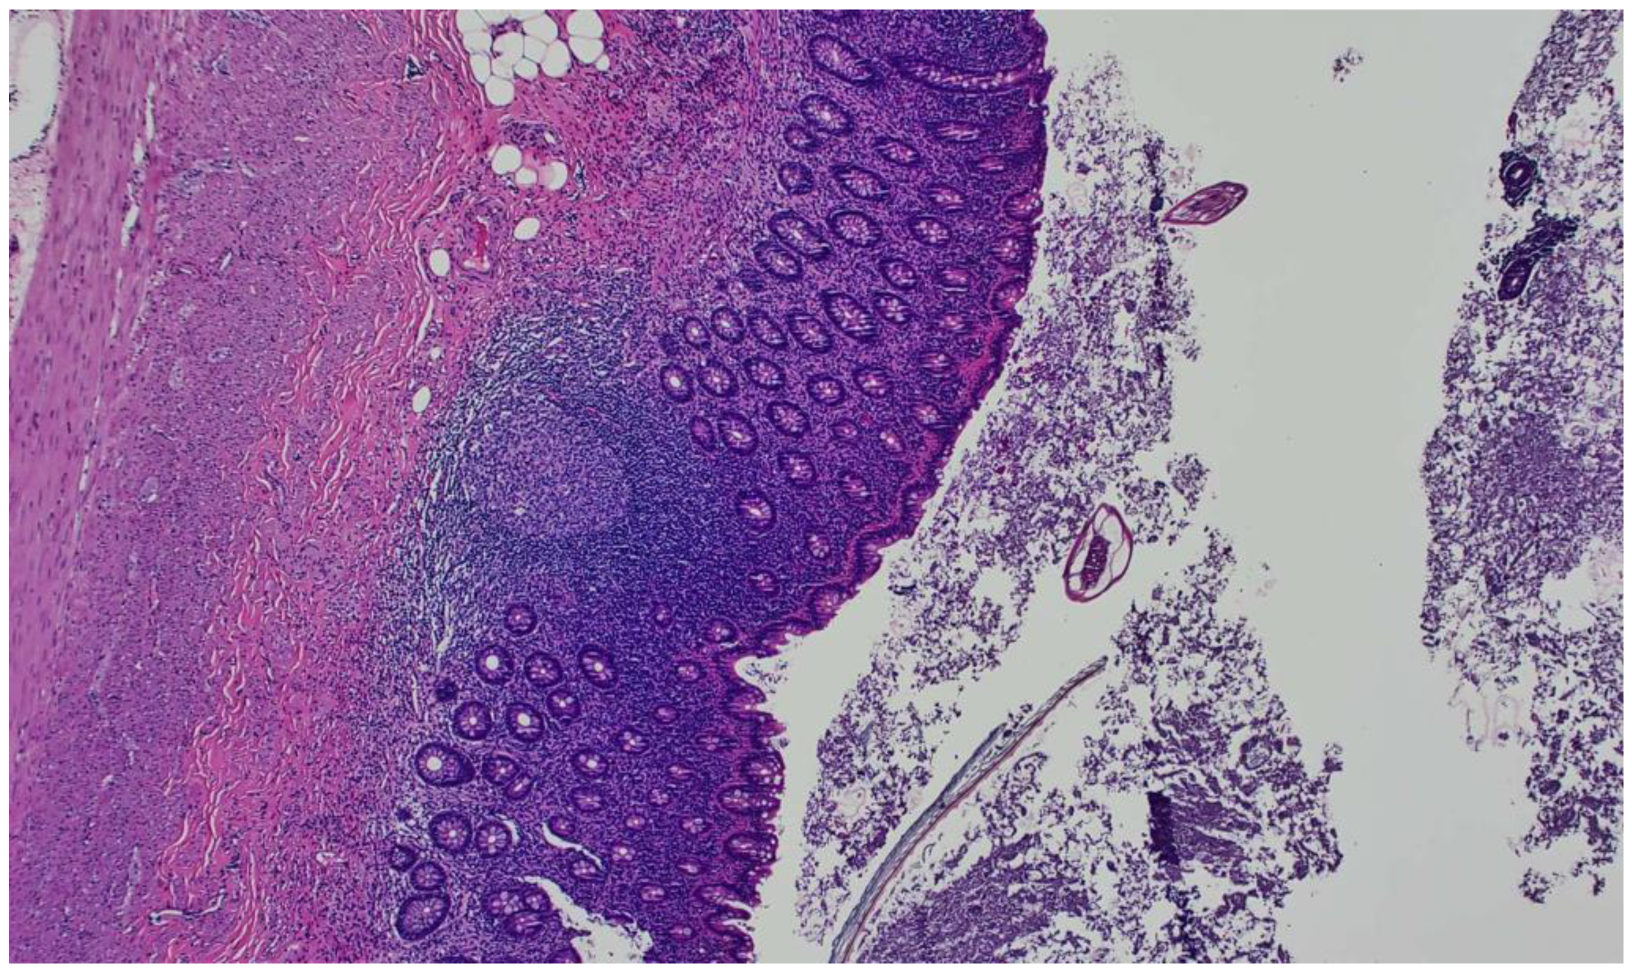

2. Case Report